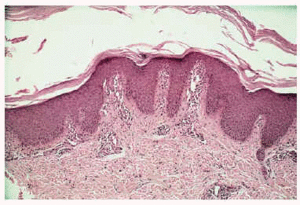

La exploración física puso de manifiesto la presencia de queratodermia palmoplantar de color rosado-amarillento, de bordes precisos y descamación laminar (fig. 1A); fisuras en los pulpejos de los dedos de las manos; placas eritematoescamosas en las rodillas, caras laterales, dorso, zonas aquíleas y maleolares externas de ambos pies (fig. 2A). No se apreciaron lesiones en el cuero cabelludo ni en las uñas ni en las mucosas.

Fig. 2.--A: placas eritematoescamosas en los dedos y el dorso de los pies antes del tratamiento. B: tras 2 meses con calcipotriol.

Establecimos, ante la clínica y los hallazgos histopatológicos sugerentes, el diagnóstico de PRP aguda infantil y comenzamos el tratamiento con calcipotriol crema dos veces al día, presentando buena tolerancia y remisión de las lesiones cutáneas tras 2 meses de tratamiento (figs. 1B y 2B). En la actualidad la paciente presenta únicamente hiperpigmentación postinflamatoria en las zonas lesionales, sin ninguna recidiva tras 7 meses de seguimiento.